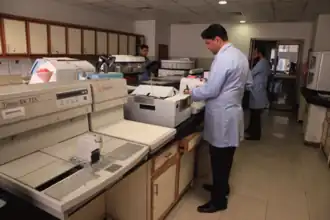

.jpg) A pathologist examines a tissue section for evidence of cancerous cells while a surgeon observes. | |

Clinical pathology

Clinical pathology is a medical specialty that is concerned with the diagnosis of disease based on the laboratory analysis of bodily fluids such as blood and urine, as well as tissues, using the tools of chemistry, clinical microbiology, hematology and molecular pathology. Clinical pathologists work in close collaboration with medical technologists, hospital administrations, and referring physicians. Clinical pathologists learn to administer a number of visual and microscopic tests and an especially large variety of tests of the biophysical properties of tissue samples involving automated analysers and cultures. Sometimes the general term "laboratory medicine specialist" is used to refer to those working in clinical pathology, including medical doctors, Ph.D.s and doctors of pharmacology.[19] Immunopathology, the study of an organism's immune response to infection, is sometimes considered to fall within the domain of clinical pathology.[20]